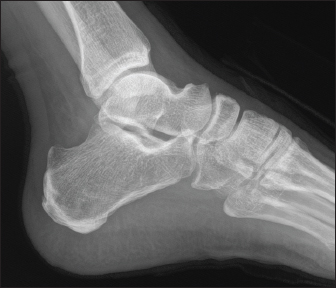

57-year-old male with diabetes, presented with complaints of intermittent fever for 4 weeks. It was associated with loss of appetite and significant loss of weight. No associated pain abdomen, vomiting, altered bowel and bladder habits. On physical examination, he had hepatomegaly. Workup for pyrexia of unknown origin was done. Mantoux test was negative. Chest X-ray showed prominent Broncho vascular markings. Contrast CT of abdomen showed splenic infarct with intraluminal short segment partial thrombosis of the proximal splenic vein along with heterogeneously enhancing subcarinal and right lower paratracheal mediastinal lymph nodes with central necrosis — probably granulomatous infection. Endobronchial ultrasound guided fine needle aspiration biopsy of mediastinal lymph nodes was done. Cytology was negative for malignancy. Histopathological report was suggestive of acute suppurative inflammation, with negative gram stain and Acid-Fast stains. But his blood culture grew B. pseudomallei and the whole clinical picture was suggestive of melioidosis. He also developed pain and swelling around left ankle joint while in hospital. On examination he had tenderness and warmth around left ankle with restricted movements. Orthopaedics consultation was obtained and an MRI ankle joint (Fig. 3) was done which showed features of acute osteomyelitis of calcaneum (multiple micro abscess) with adjacent intermuscular and fascial abscesses. Ultrasound guided aspiration of the plantar abscess was done and pus was aspirated. Culture grew B. Pseudomallei. The patient was diagnosed with osteomyelitis caused by melioidosis and was treated with intravenous Meropenem for 6 weeks, followed by oral cotrimoxazole for another six months. The patient had a good recovery and was followed up in the outpatient clinic.

Fig. 3. MRI Rt. foot—patient 2.